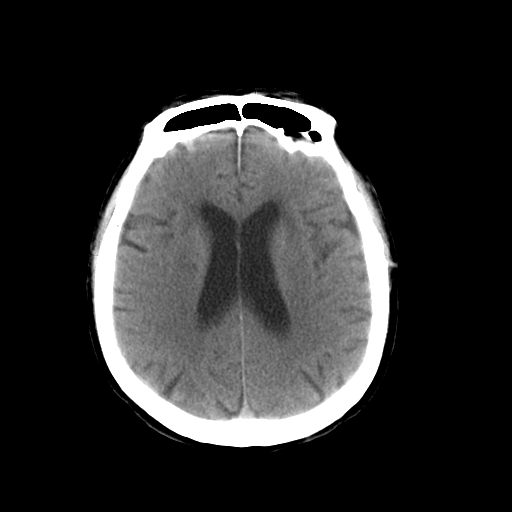

以下是引用dsl555在2008-11-11 18:52:00的发言:[br]四脑室后上方,四叠体池上方可见一小结节状稍高等密度影,比40天略大,建议mri或增强

以下是引用zjzjr在2008-11-12 8:28:00的发言:[br]四脑室后方略高密度影,周围环一低密度水肿带,四脑室受压变形,考虑小脑蚓部血肿吸收期或占位,建议增强